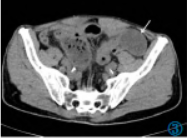

患者于检查当日(8月30日)夜间出现双侧足背、小腿伸面多发性皮下淤点,大小形态不等,颜色为深红色,压之不褪色。诊断为AAP。临床予以“甲强龙40mgivgttqd×3d”抗炎、抗过敏以及补液对症等治疗,患者腹痛明显好转,下肢皮疹明显消退,复查CT显示,肠壁水肿好转,肠腔扩张管径约为3.4cm,系膜渗出改变好转,腹盆腔积液吸收(图3)。

图3AAP好转CT表现。腹部CT平扫显示小肠壁水肿好转,肠腔扩张(白色箭头所指),盆腔积液吸收。